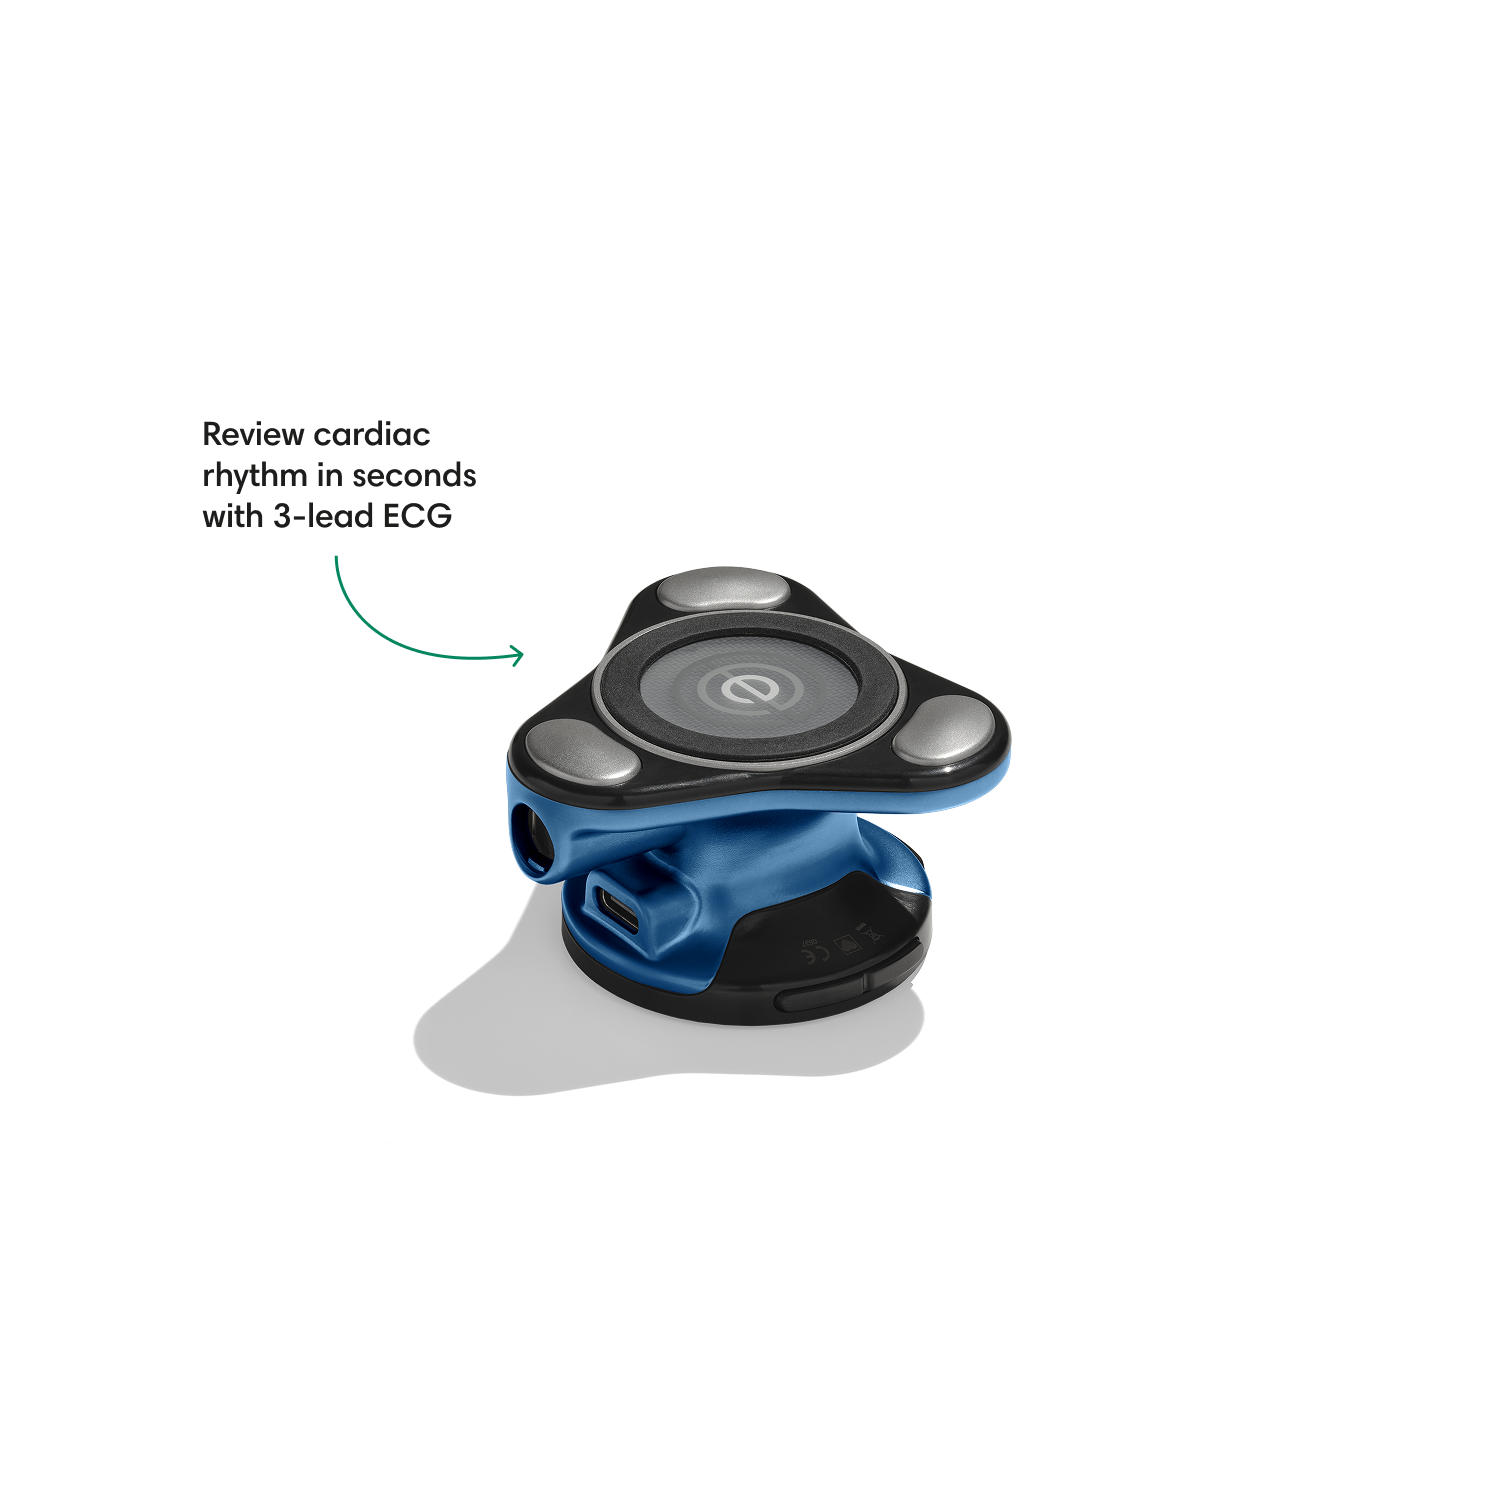

Go beyond sound alone.

For the first time ever, measure heart rate, visualize 3-lead ECG, and see detection results — right on a built-in, full-color display.